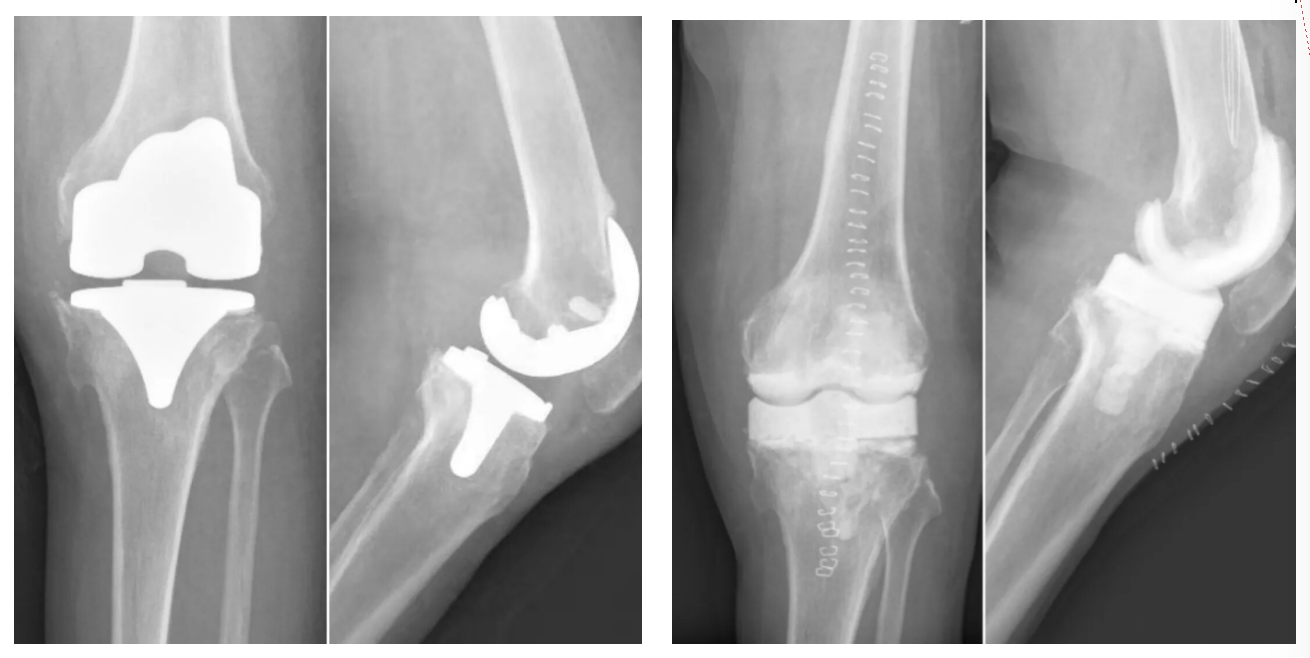

经过周密准备,谢锦伟团队为阿某实施了一期手术。手术目标明确——1.取出假体:将初次植入的已失效的人工关节取出;2.彻底清创:完整切除所有被感染的组织;3.植入“抗生素骨水泥临时假体”:该“占位器”能在局部持续释放高浓度抗生素,彻底净化关节环境,为二期手术植入全新的假体奠定坚实基础。“首期手术是决胜的关键,如同一次彻底的‘大扫除’。”谢锦伟比喻道。

(抗生素骨水泥临时假体置入)